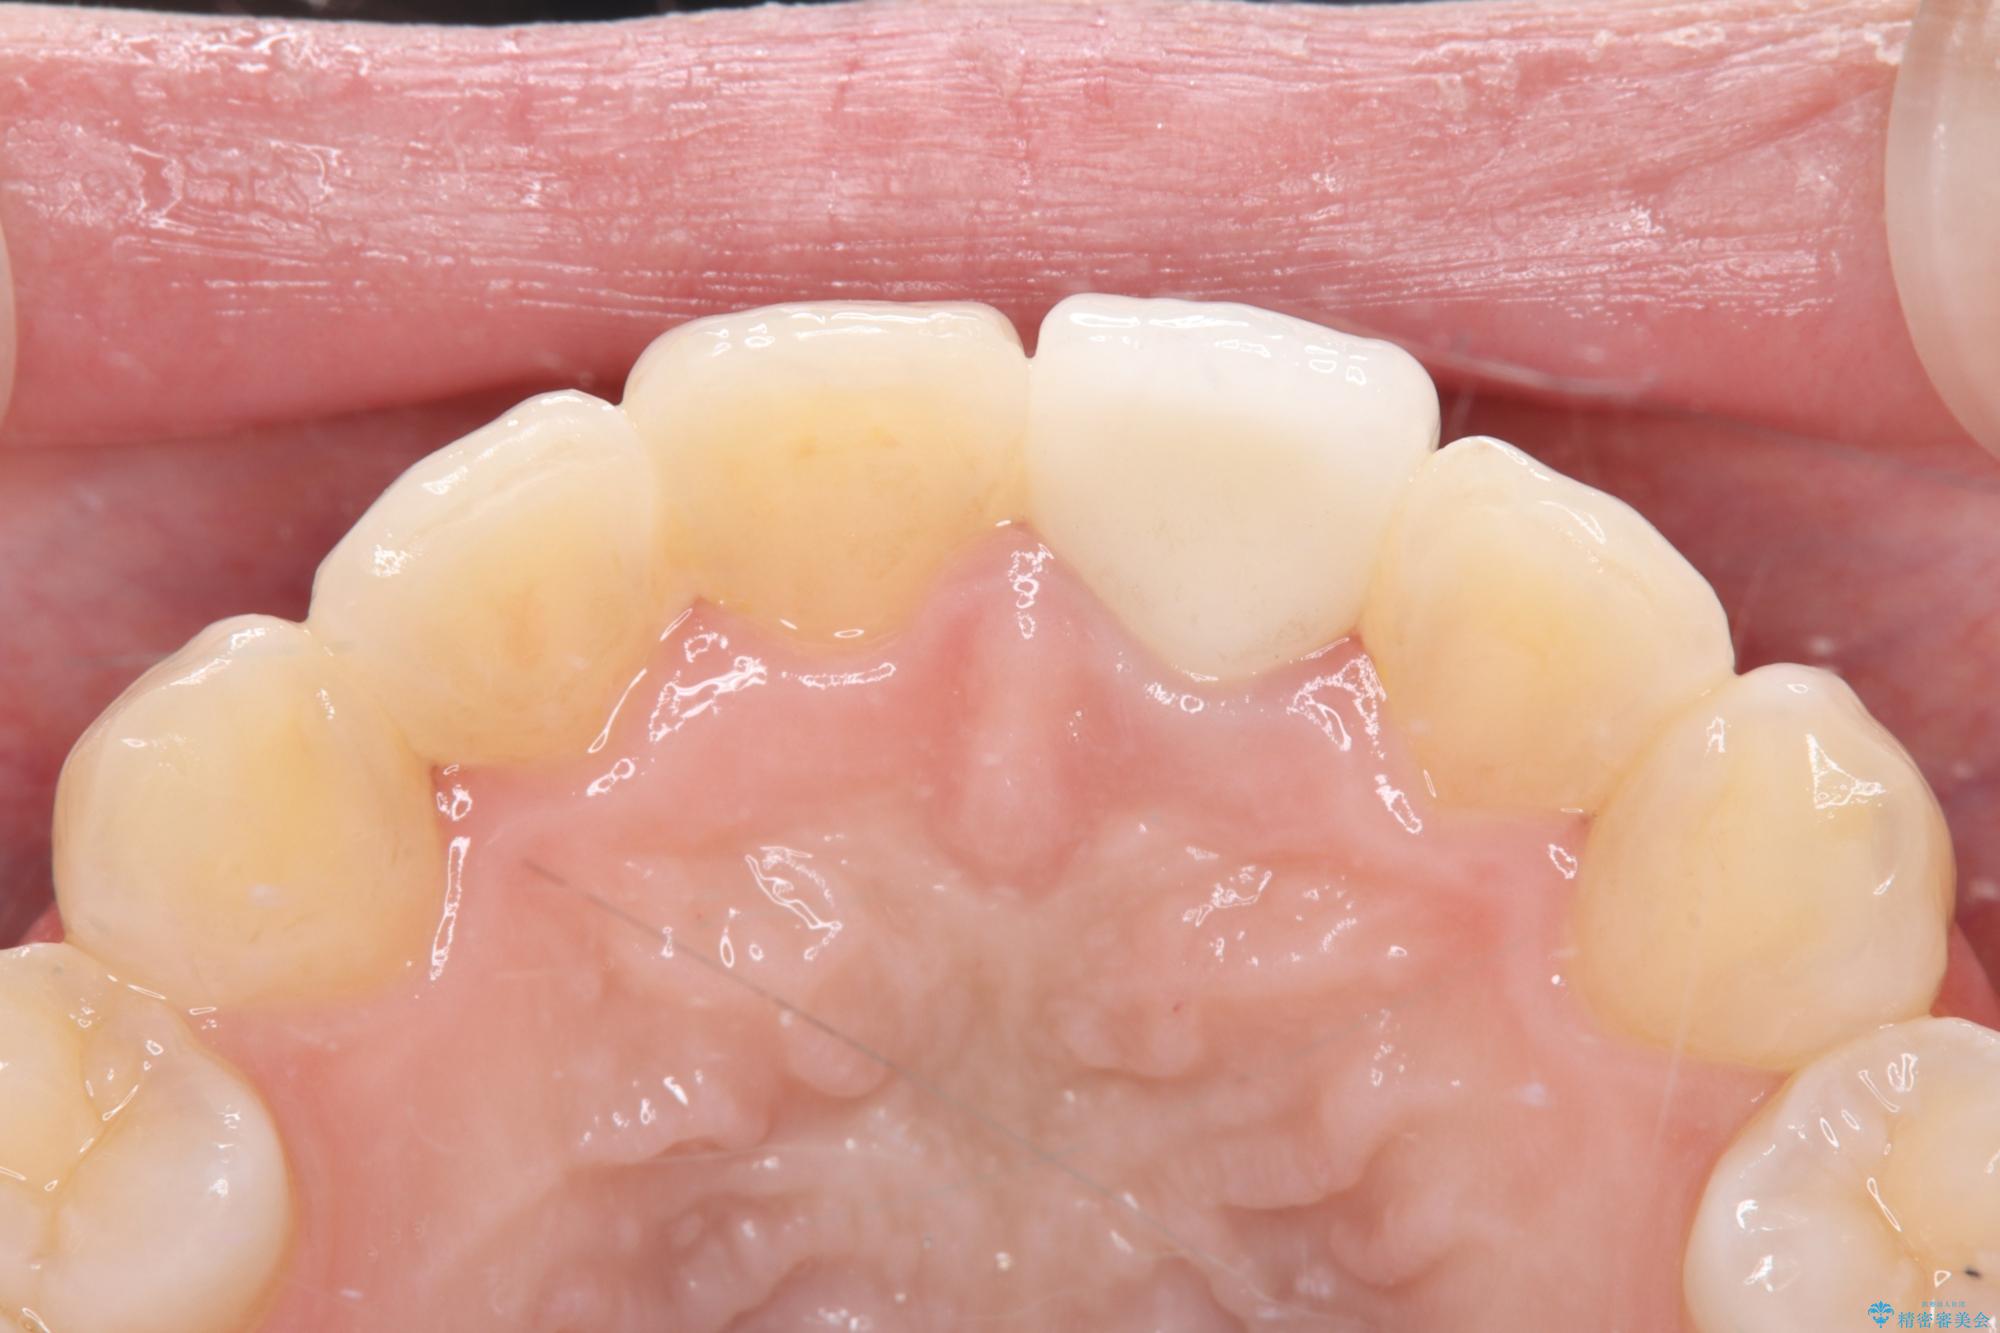

そこで、まずは土台を外して根の内部をきれいにする再根管治療を行い、基礎をやり直した上で、透明感の高いオールセラミッククラウンで被せ直す治療計画を立案。単に白くするだけでなく、再発を防ぎ、長期的に美しい状態を保つことを目指しました。

オールセラミッククラウンによる修復: 最終的な被せ物には、一切の金属を使用しないオールセラミックを選択。隣の天然歯と色調や透明感を精密に合わせることで、どこを治療したかわからないほど自然な仕上がりとなりました。